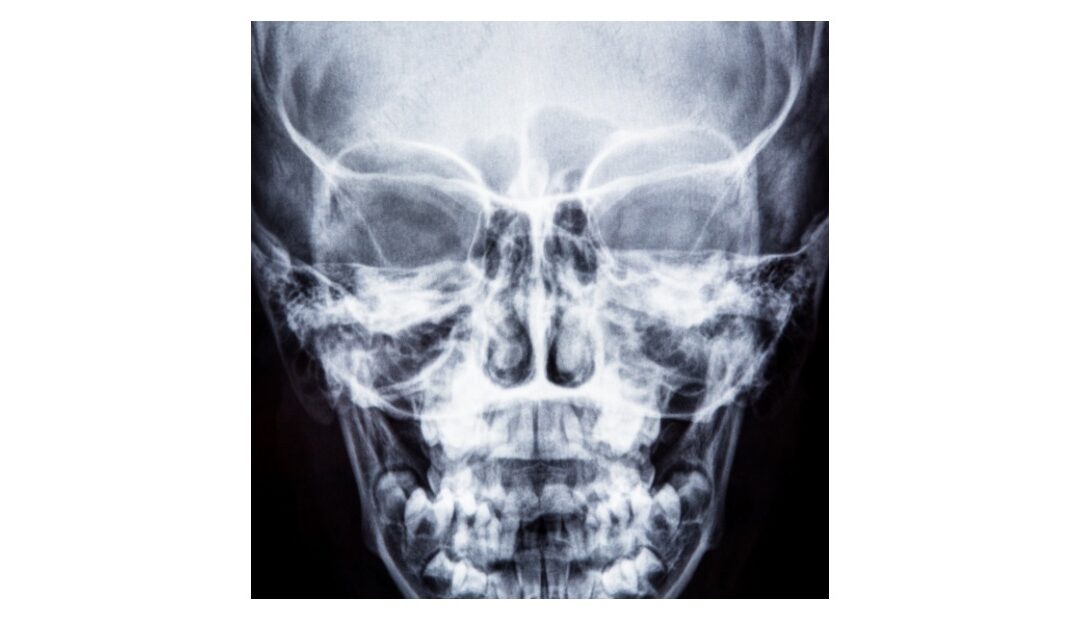

Raio X Da Face: O Que é, Pare Que Serve E Como é Feito

telemedicinamorsch.com.br

telemedicinamorsch.com.br

Raio X Da Face: O Que é, Pare Que Serve E Como é Feito

telemedicinamorsch.com.br

telemedicinamorsch.com.br

Raio X Da Face Foto De Stock. Imagem De Ciência, Ossos - 1792828

pt.dreamstime.com

pt.dreamstime.com

raio rayon visage